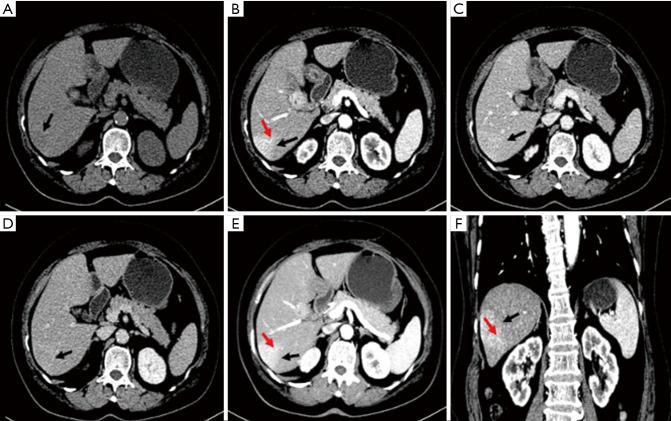

A 69-year-old woman presented with intermittent right upper abdominal discomfort. Imaging revealed an ovoid liver mass. She was in good overall health, with no history of chronic diseases, hepatitis, tuberculosis, allergies, surgeries, trauma, or blood transfusions. Laboratory tests were normal, with negative results for carcinoembryonic antigen and alpha-fetoprotein (AFP). After computed tomography (CT) and magnetic resonance imaging (MRI) examinations, the patient underwent laparoscopic liver tumor resection.

一名69岁女性出现间歇性右上腹不适。影像学检查发现肝脏有一个椭圆形肿块。她整体健康状况良好,无慢性疾病、肝炎、结核、过敏、手术、外伤或输血史。实验室检查正常,癌胚抗原和甲胎蛋白(AFP)结果均为阴性。经过计算机断层扫描(CT)和磁共振成像(MRI)检查后,患者接受了腹腔镜肝肿瘤切除术。

结论

HEAML这种罕见肿瘤具有一定程度的恶性潜能,主要影响老年女性。CT和MRI上的某些特征有助于其与其他肝内病变相鉴别。在我们的病例中,采用了多模式方法,对肿瘤进行详细的影像学分析可为其准确诊断提供参考。